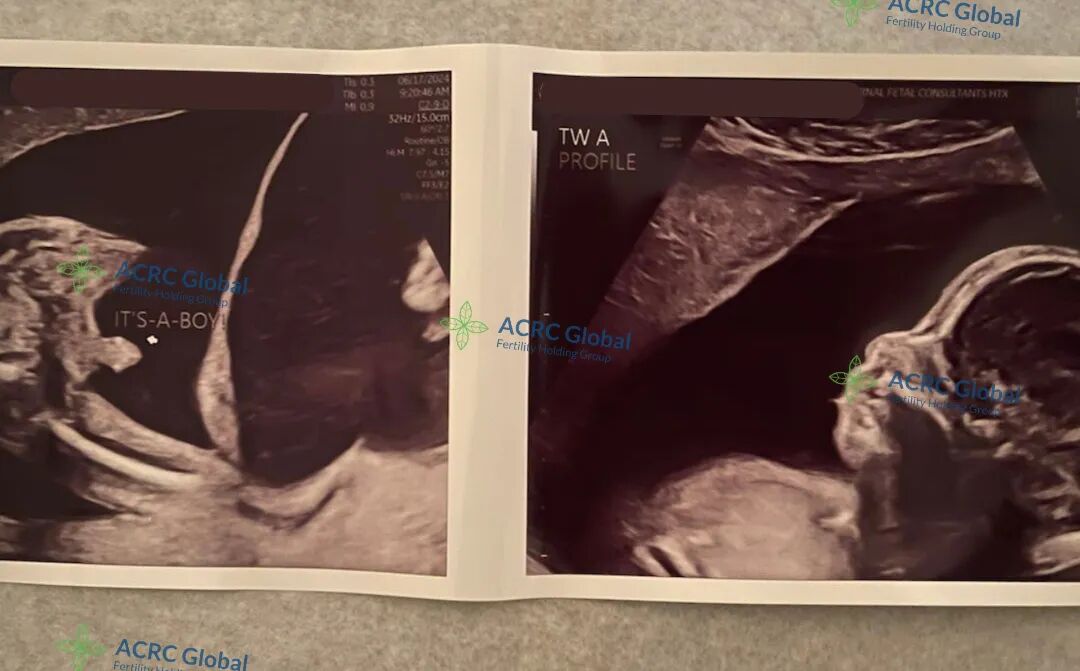

我们的单身准妈妈又收到了爱妈J最新的B超检查照片。可爱的双胞胎宝宝已经21周了,两位小家伙都非常健康,已经可以清晰地看到是两个可爱的男宝宝。准妈妈年轻时一心投入事业,无暇顾及人生大事。中年事业有成后,看到周围朋友都有了可爱的孩子,感到非常遗憾,觉得错过了最佳的生育年龄。于是她找到了我们,希望在爱妈的帮助下,也能拥有一个幸福的家庭。

她通过精子库选择了一位优秀的男性,制作了优质的胚胎,并在爱妈J的帮助下顺利移植了两个胚胎。为了实现她的家庭生育计划,她决定先迎来两个男宝宝。这项技术通过结合试管婴儿技术和植入前遗传测试(PGT)来实现。PGT不仅可以筛查胚胎的遗传疾病,还能确定胚胎的染色体性别,从而允许准父母选择植入所期望性别的胚胎。